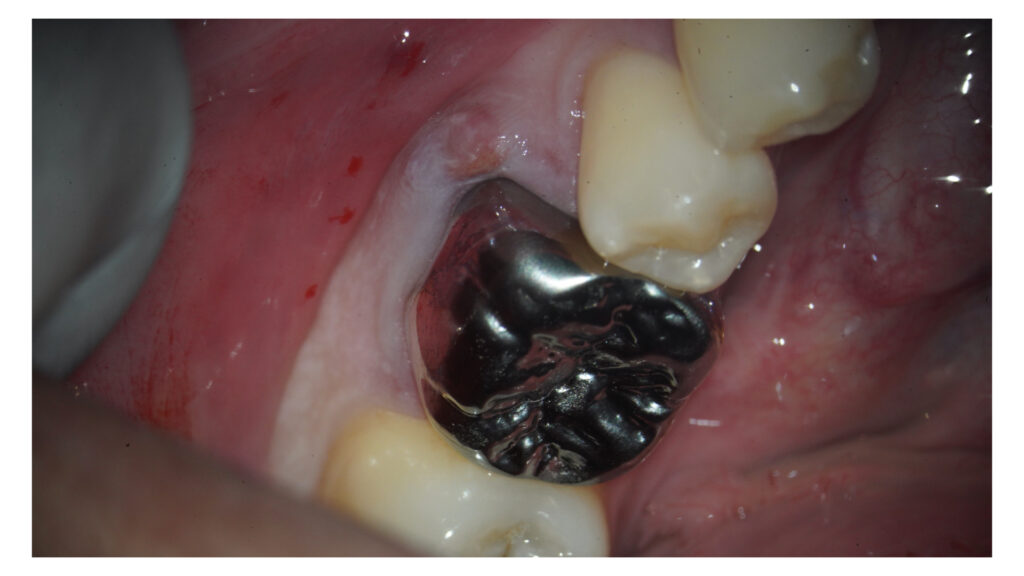

インプラント治療に向けたGBR(骨増成)およびソケットプリザベーションをCytoplast TXT-200を用いてオープンバリアメンブレンテクニックにて行いました。

メンブレン設置に向けてエンベロープ形成を事前に行なっています。

今後2週間程度でメンブレンを除去して、インプラント手術を1ヶ月後に予定しています。